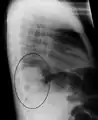

A black and white X-ray picture showing a triangle white area on the left side. A circle highlights the area.

A chest X-ray showing a very prominent wedge-shape bacterial pneumonia in the right lung